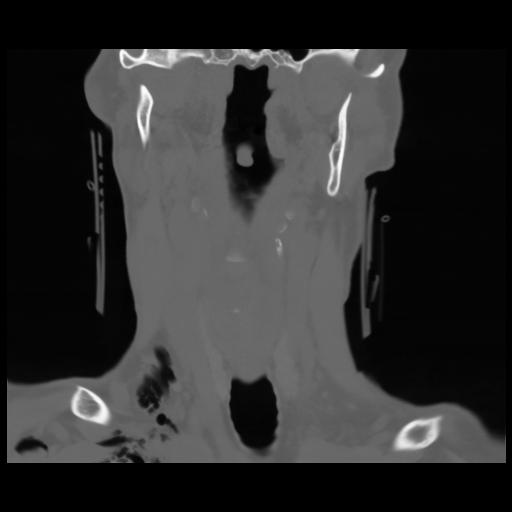

13 P.BLANDAS,,Coronal,2.000,P.BLANDAS,Coronal,